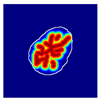

| True label: Crescentic |  |  |  |  |  |

| single-multiclass: Crescentic p = 0.999, IoU = 0.154 | |||||

| multiple-binary: Crescentic p = 1.000, IoU = 0.128 | |||||

| Spatially guided: Crescentic p = 0.979, IoU = 0.740 | |||||